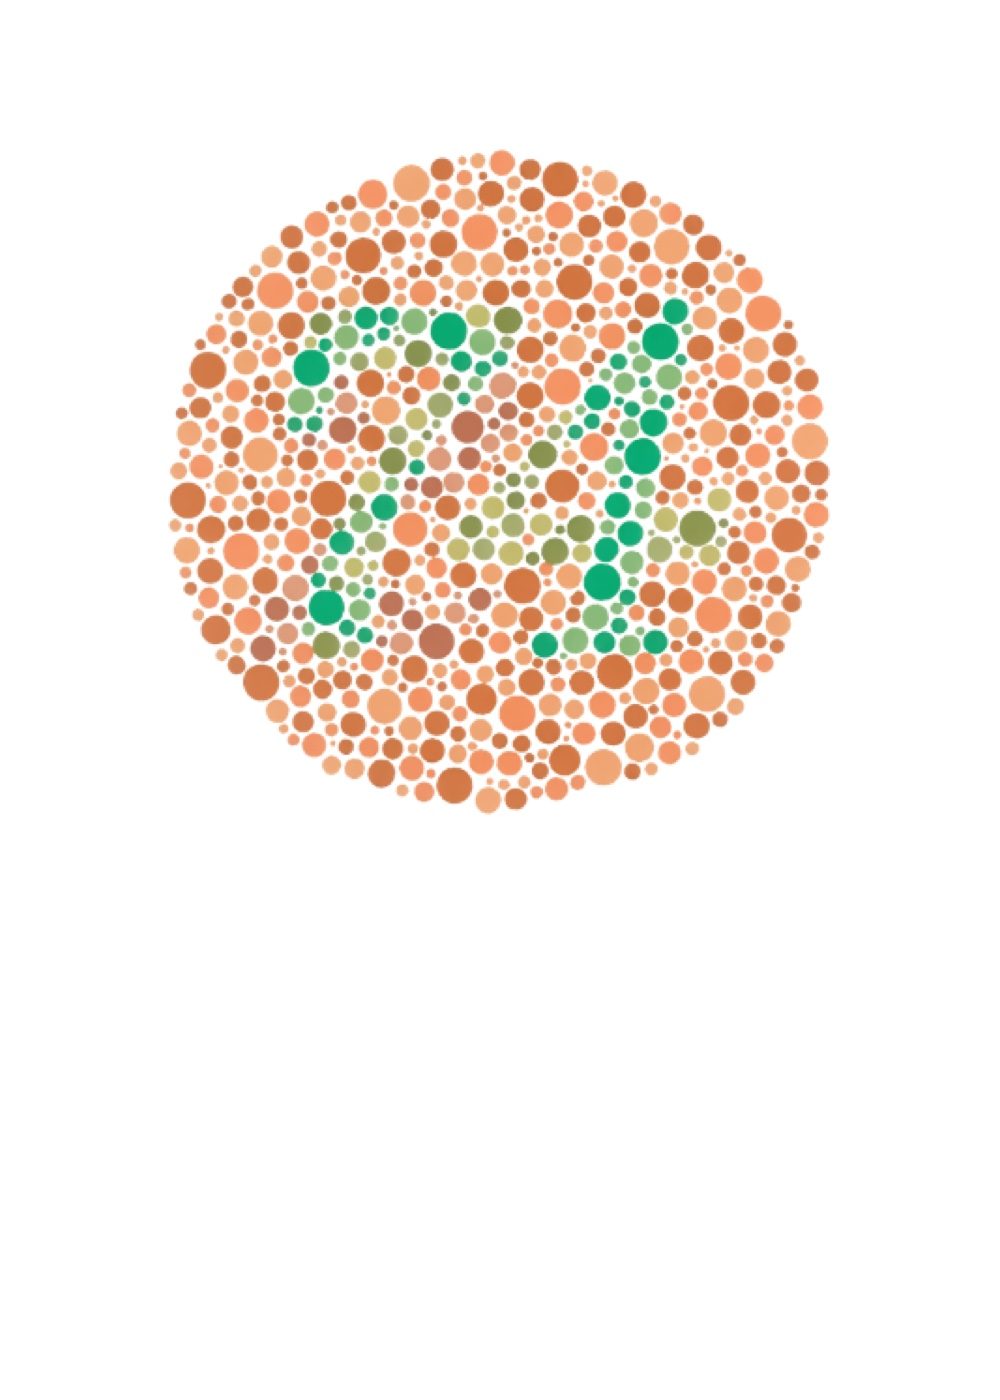

Test del Color

Es una prueba utilizada para evaluar la percepción del color y anomalías en la visión cromática.